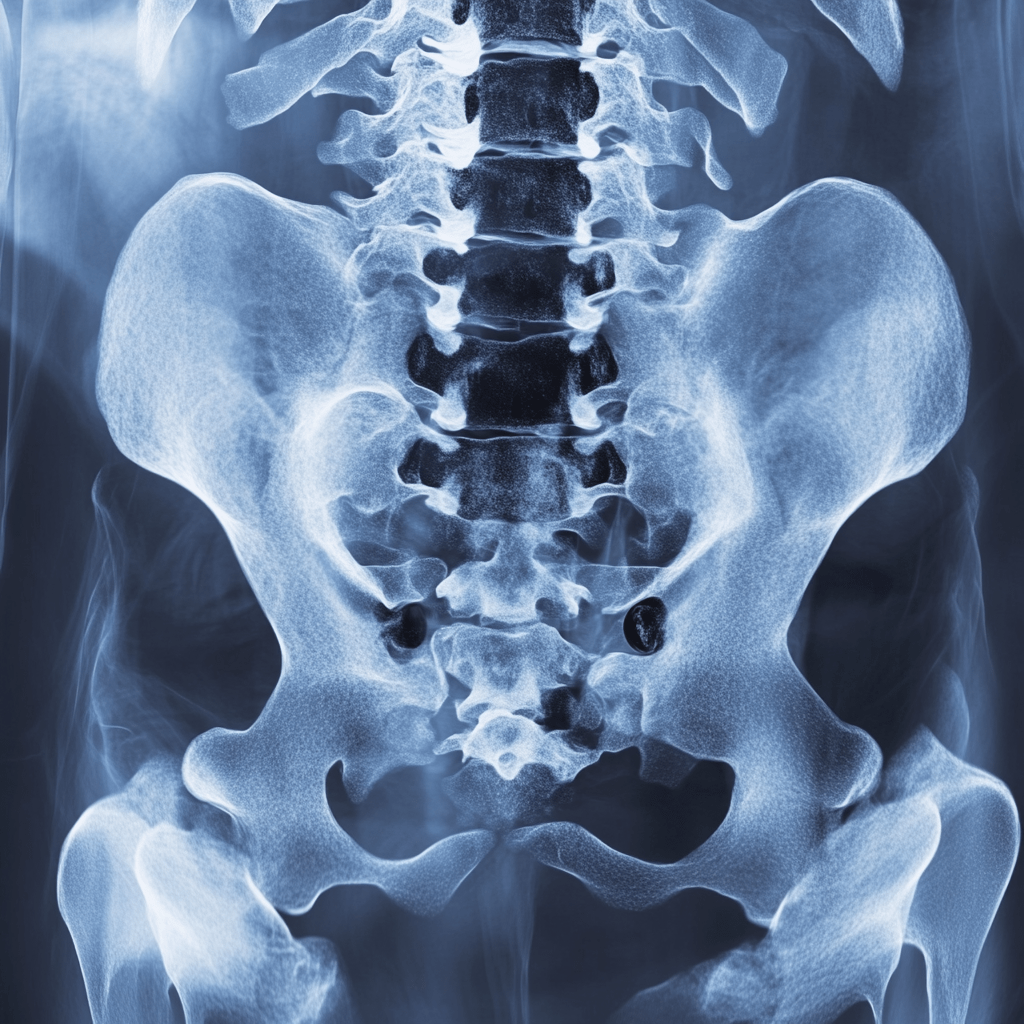

Tratamientos Avanzados para la Columna Vertebral

El dolor crónico de columna es la principal causa de incapacidad en el país.

Este padecimiento requiere de un tratamiento específico y adecuado para cada caso.

Te ofrecemos un tratamiento integral y personalizado desde el diagnóstico hasta la recuperación. Al elegirnos, obtienes: